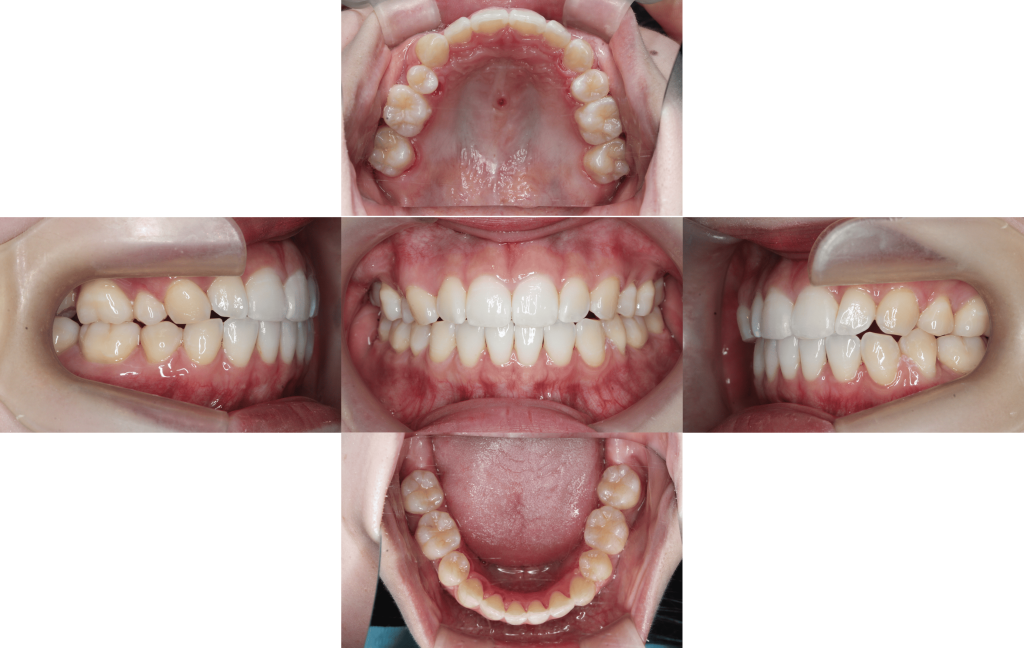

Before

初診